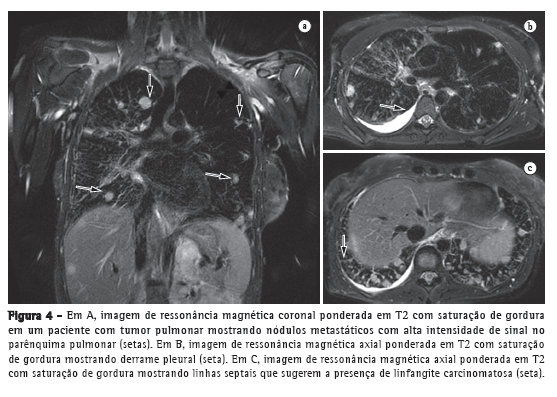

Por ser mais eficaz que os métodos convencionais de estadiamento para determinar o estágio TNM, a combinação PET/TC parece ser uma ferramenta de primeira linha para o estadiamento do câncer de pulmão. Entretanto, a RM tem assumido um papel cada vez mais importante nesse cenário. A Figura 4 mostra a habilidade da RM para demonstrar, de forma clara, metástases locais de um tumor pulmonar. Relatou-se que a combinação PET/TC não é capaz de revelar metástases microscópicas em aproximadamente 20% dos pacientes submetidos a tratamento cirúrgico.(12) Estudos anteriores demonstraram que a RM de corpo inteiro tem precisão aceitável e que sua eficácia no estadiamento do câncer de pulmão é comparável àquela da combinação PET/TC.(13) Cada uma dessas duas modalidades de imagem tem suas vantagens(12); a RM de corpo inteiro é melhor para detectar metástase cerebral e hepática, ao passo que a combinação PET/TC é melhor para detectar metástase em linfonodos e tecidos moles. Para a avaliação de áreas submetidas a radioterapia, a difusão é uma técnica promissora.(12) A RM de corpo inteiro com imagem ponderada em difusão pode ser utilizada para a avaliação do estágio M (metástase) em pacientes com CPCNP e revelou-se tão acurada quanto a combinação PET/TC.(14)